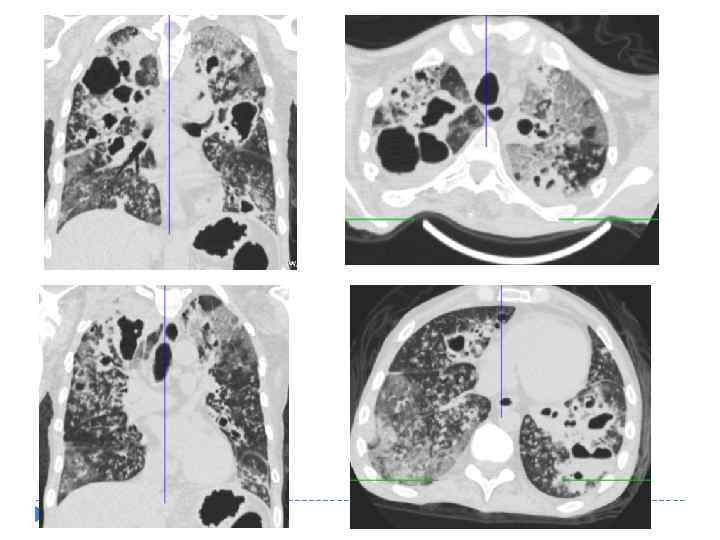

ТУБЕРКУЛЕМА ЛЕГКИХ Характеризуется наличием капсулированного казеоза округлой формы более 1 см в диаметре. Туберкулеме соответствует «синдром круглой (овальной) тени» .

ТУБЕРКУЛЕМА ЛЕГКИХ Характеризуется наличием капсулированного казеоза округлой формы более 1 см в диаметре. Туберкулеме соответствует «синдром круглой (овальной) тени» .